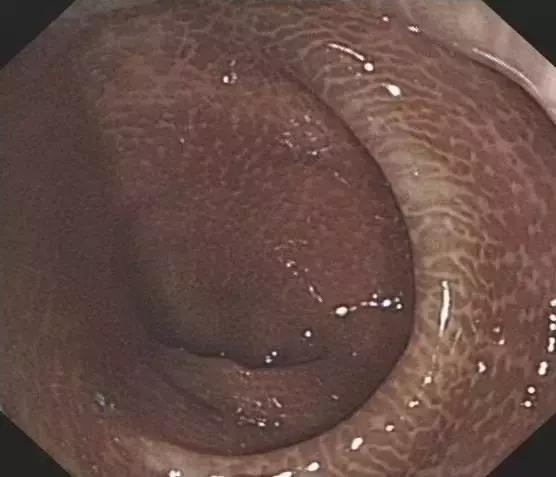

而长期使用这类刺激*药性**物,不仅会对药物形成依赖,还会对肠道的蠕动及分泌功能有所损伤,导致结肠黑变病,久而久之甚至引起癌变。

▲黑变病结肠

然而,结肠黑变病还不是最可怕的,最可怕的是滥用泻剂对于肠功能和肠动力的损害,这些是不可逆的!